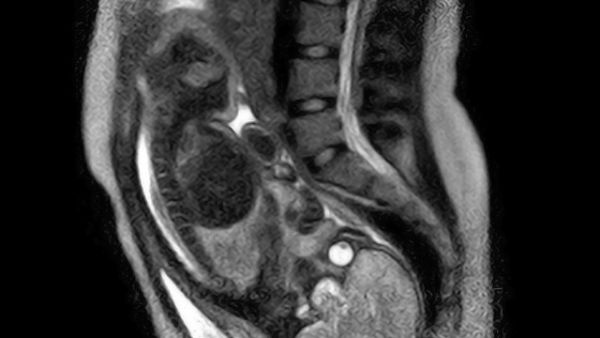

Ακόμα κι αν έχουμε βιώσει την εμπειρία του τοκετού, πάντα θα βρίσκουμε εντυπωσιακά τα βίντεο και τις φωτογραφίες μιας γέννας. Αυτό το ασύλληπτο θαύμα που συντελείται μας επιτρέπει να ανακαλύπτουμε κάθε φορά και μια νέα προοπτική στη διαδικασίας της γέννησης. Ενώ όλοι μας λίγο-πολύ έχουμε δει στιγμιότυπα από τη στιγμή της γέννησης ενός παιδιού, είναι βέβαιο ότι δεν έχουμε ξαναδεί κάτι αντίστοιχο με το παρακάτω απίστευτο επιστημονικό βίντεο. Αποτελείται από πλάνα που τραβήχτηκαν σε ανοιχτό μαγνητικό τομογράφο, όπου βλέπουμε τι συμβαίνει στη μήτρα μιας 24χρονης γυναίκας τη στιγμή που φέρνει στον κόσμο το 2,5 κιλών αγοράκι της. Το λευκό σχήμα που φαίνεται να πιέζει το κεφαλάκι του μωρού είναι ο αμνιακός σάκος με το αμνιακό υγρό μέσα του, πράγμα που μαρτυρά ότι δεν είχαν σπάσει τα νερά της μαμάς μέχρι τη στιγμή της γέννας. Κι ενώ θα ήταν συναρπαστικό να δούμε τη διαδικασία του τοκετού να ολοκληρώνεται, το βίντεο σταματά τη στιγμή που βγαίνει το κεφαλάκι του μωρού, προκειμένου να προστατευτεί η ακοή του από τον ήχο του τομογράφου. Το συγκεκριμένο βίντεο είναι μέρος μιας μελέτης που δημοσιεύτηκε στην επιστημονική επιθεώρηση «American Journal of Obstetrics & Gynecology», με τους ειδικούς να τονίζουν ότι «η σε βάθος κατανόηση της μητρικής και εμβρυϊκής ανατομίας και φυσιολογίας είναι απαραίτητα για τη σωστή διαχείριση της διαδικασίας του τοκετού».

Βίντεο: Ο τοκετός όπως δεν τον έχετε ξαναδεί!